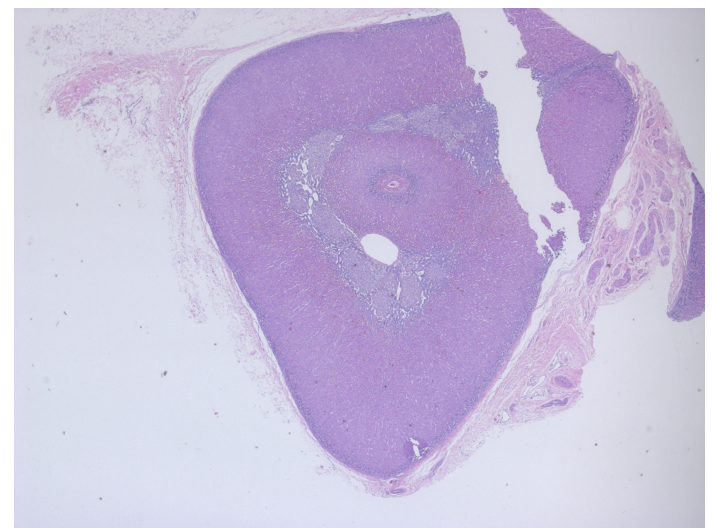

Black –> thyroid

Red –> parathyroid

parathyroid capsule